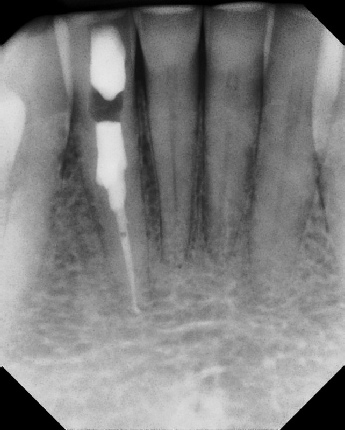

COMPLICATED ANATOMY LARGE LESIONS CALCIFIED CANALS PERFORATION / RESORPTION SEPARATED INSTRUMENTS SURGICAL CASES RETREATMENT / pOST REMOVAL OPEN APICES ACCESS THRU CROWNS Root Canal Case Portfolio